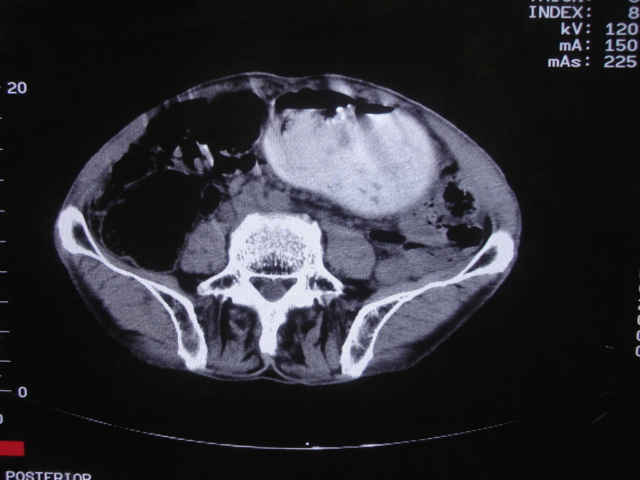

以下是引用深泽交通医院在2008-7-17 12:39:00的发言:[br]胃下垂;胃窦占位

以下是引用前行在2008-7-17 12:57:00的发言:[br]建议胃镱检查

以下是引用杀毒软件在2008-7-17 16:45:00的发言:[br][br] 建议胃镱检查!考虑胃窦部占位